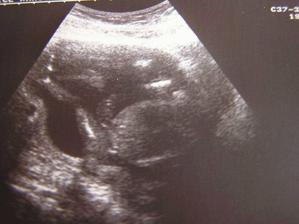

SRPŇÁTKA 2007 - fotky UTZ

album věnované mimískům, které se narodí v srpnu 2007 a jejich maminkám ze "Společného termínu SRPEN"